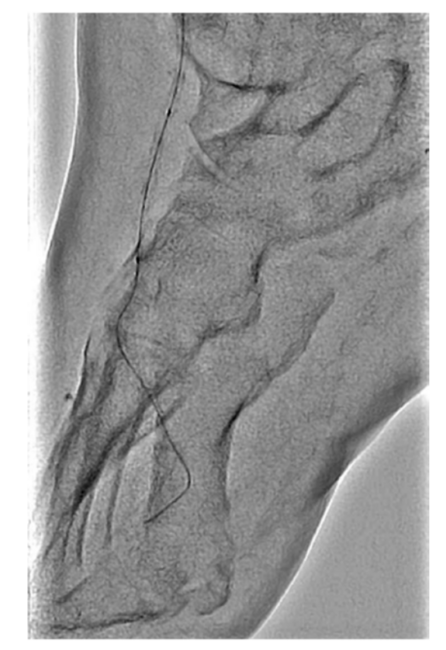

On examination, his right dorsal pedis and posterior tibialis pulses were absent. His right heel had a mature eschar on the posterior aspect with no erythema, drainage, or odor noted in addition to wounds involving his second to fifth digits. Bedside Doppler showed a diminished signal at the dorsal pedis and absent signal at the right posterior tibial. X-ray of the foot demonstrated no evidence of osteomyelitis. His vascular arterial Duplex ultrasound showed an occluded right posterior tibial DVA. The distal anterior tibial artery was severely diseased with a distal occlusion and a monophasic waveform (Figure 1A and 1B). The distal peroneal and posterior tibial arteries were occluded. The plantar veins were studied with ultrasound for possible targets for hybrid DVA using a great saphenous vein to medial marginal vein bypass; however, this was not favored after discussing with vascular surgery. He was evaluated for right below knee amputation which he refused. He was then transferred to our facility to consider other treatment options for revascularization as a last resort. He had a peripheral angiogram that showed a patent distal aorta, iliac arteries, and femoropopliteal segments. The right anterior tibial artery was diffusely diseased with a 90% critical stenosis in its distal segment (Figure 2). The right distal peroneal, posterior tibial arteries and the right posterior DVA were occluded. After careful analysis of the angiogram, we proceeded with an intervention to the anterior tibial artery to establish direct foot perfusion. The left common femoral artery was accessed under ultrasound guidance using a micropuncture needle. A 4F IMA diagnostic catheter and a 0.035 angled Glidewire were used to access the contralateral right common iliac artery. The right SFA and profunda femoral arteries were heavily calcified without severe obstructive disease. The wire was advanced into the right popliteal artery and a 5F by 90 cm Cook Flexor Shuttle was advanced to the origin of the right anterior tibial artery for good support. An Asahi Sion Black 0.014 x 300 cm guidewire was advanced and used to cross the distal anterior tibial stenosis into the dorsal pedis artery. The distal wire was advanced into the first dorsal metatarsal branch after several attempts to wire across the pedal loop. A Corsair Asahi 150 cm microcatheter was then advanced into the dorsal pedis artery and selective foot angiogram was performed. A magnified view of the right foot showed a chronic total occlusion of the dorsal pedis (Figure 3). Laser atherectomy was performed with Philips Turbo Elite 0.9 mm catheter from the origin of the anterior tibial artery to the beginning of the dorsal pedis artery at 80/80 fluency/rate (Figure 4). This was followed by balloon angioplasty with coronary balloons since other balloons will not cross at rated pressure with multiple prolonged 5-minute inflations each of the entire vessel. A Coyote 2.5 x 220 mm balloon was used to further postdilate the anterior tibial artery obtaining excellent angiographic result with improvement of the blood flow into the dorsal pedis as well as the collaterals to the posterior tibial and its plantar branches. The patient’s ischemic rest pain resolved and he was followed linearly along wound care with significant improvement few weeks later.